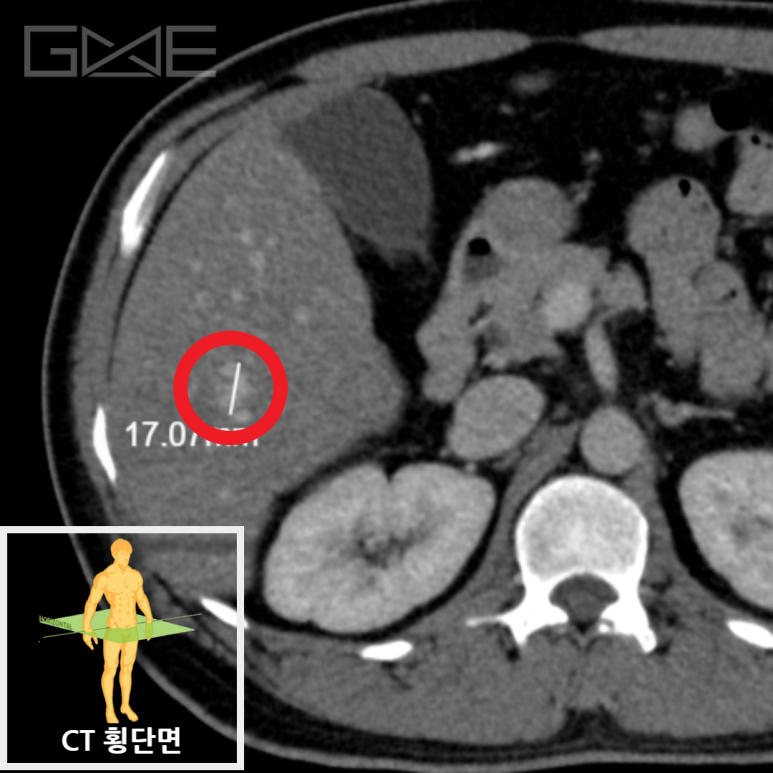

간 실질 전반에 지방간 소견이 보이며, S6 부위에 1.7cm 크기의 혈관종 가능 병변이 관찰됩니다.

• 간CT 횡단면 간CT 횡단면